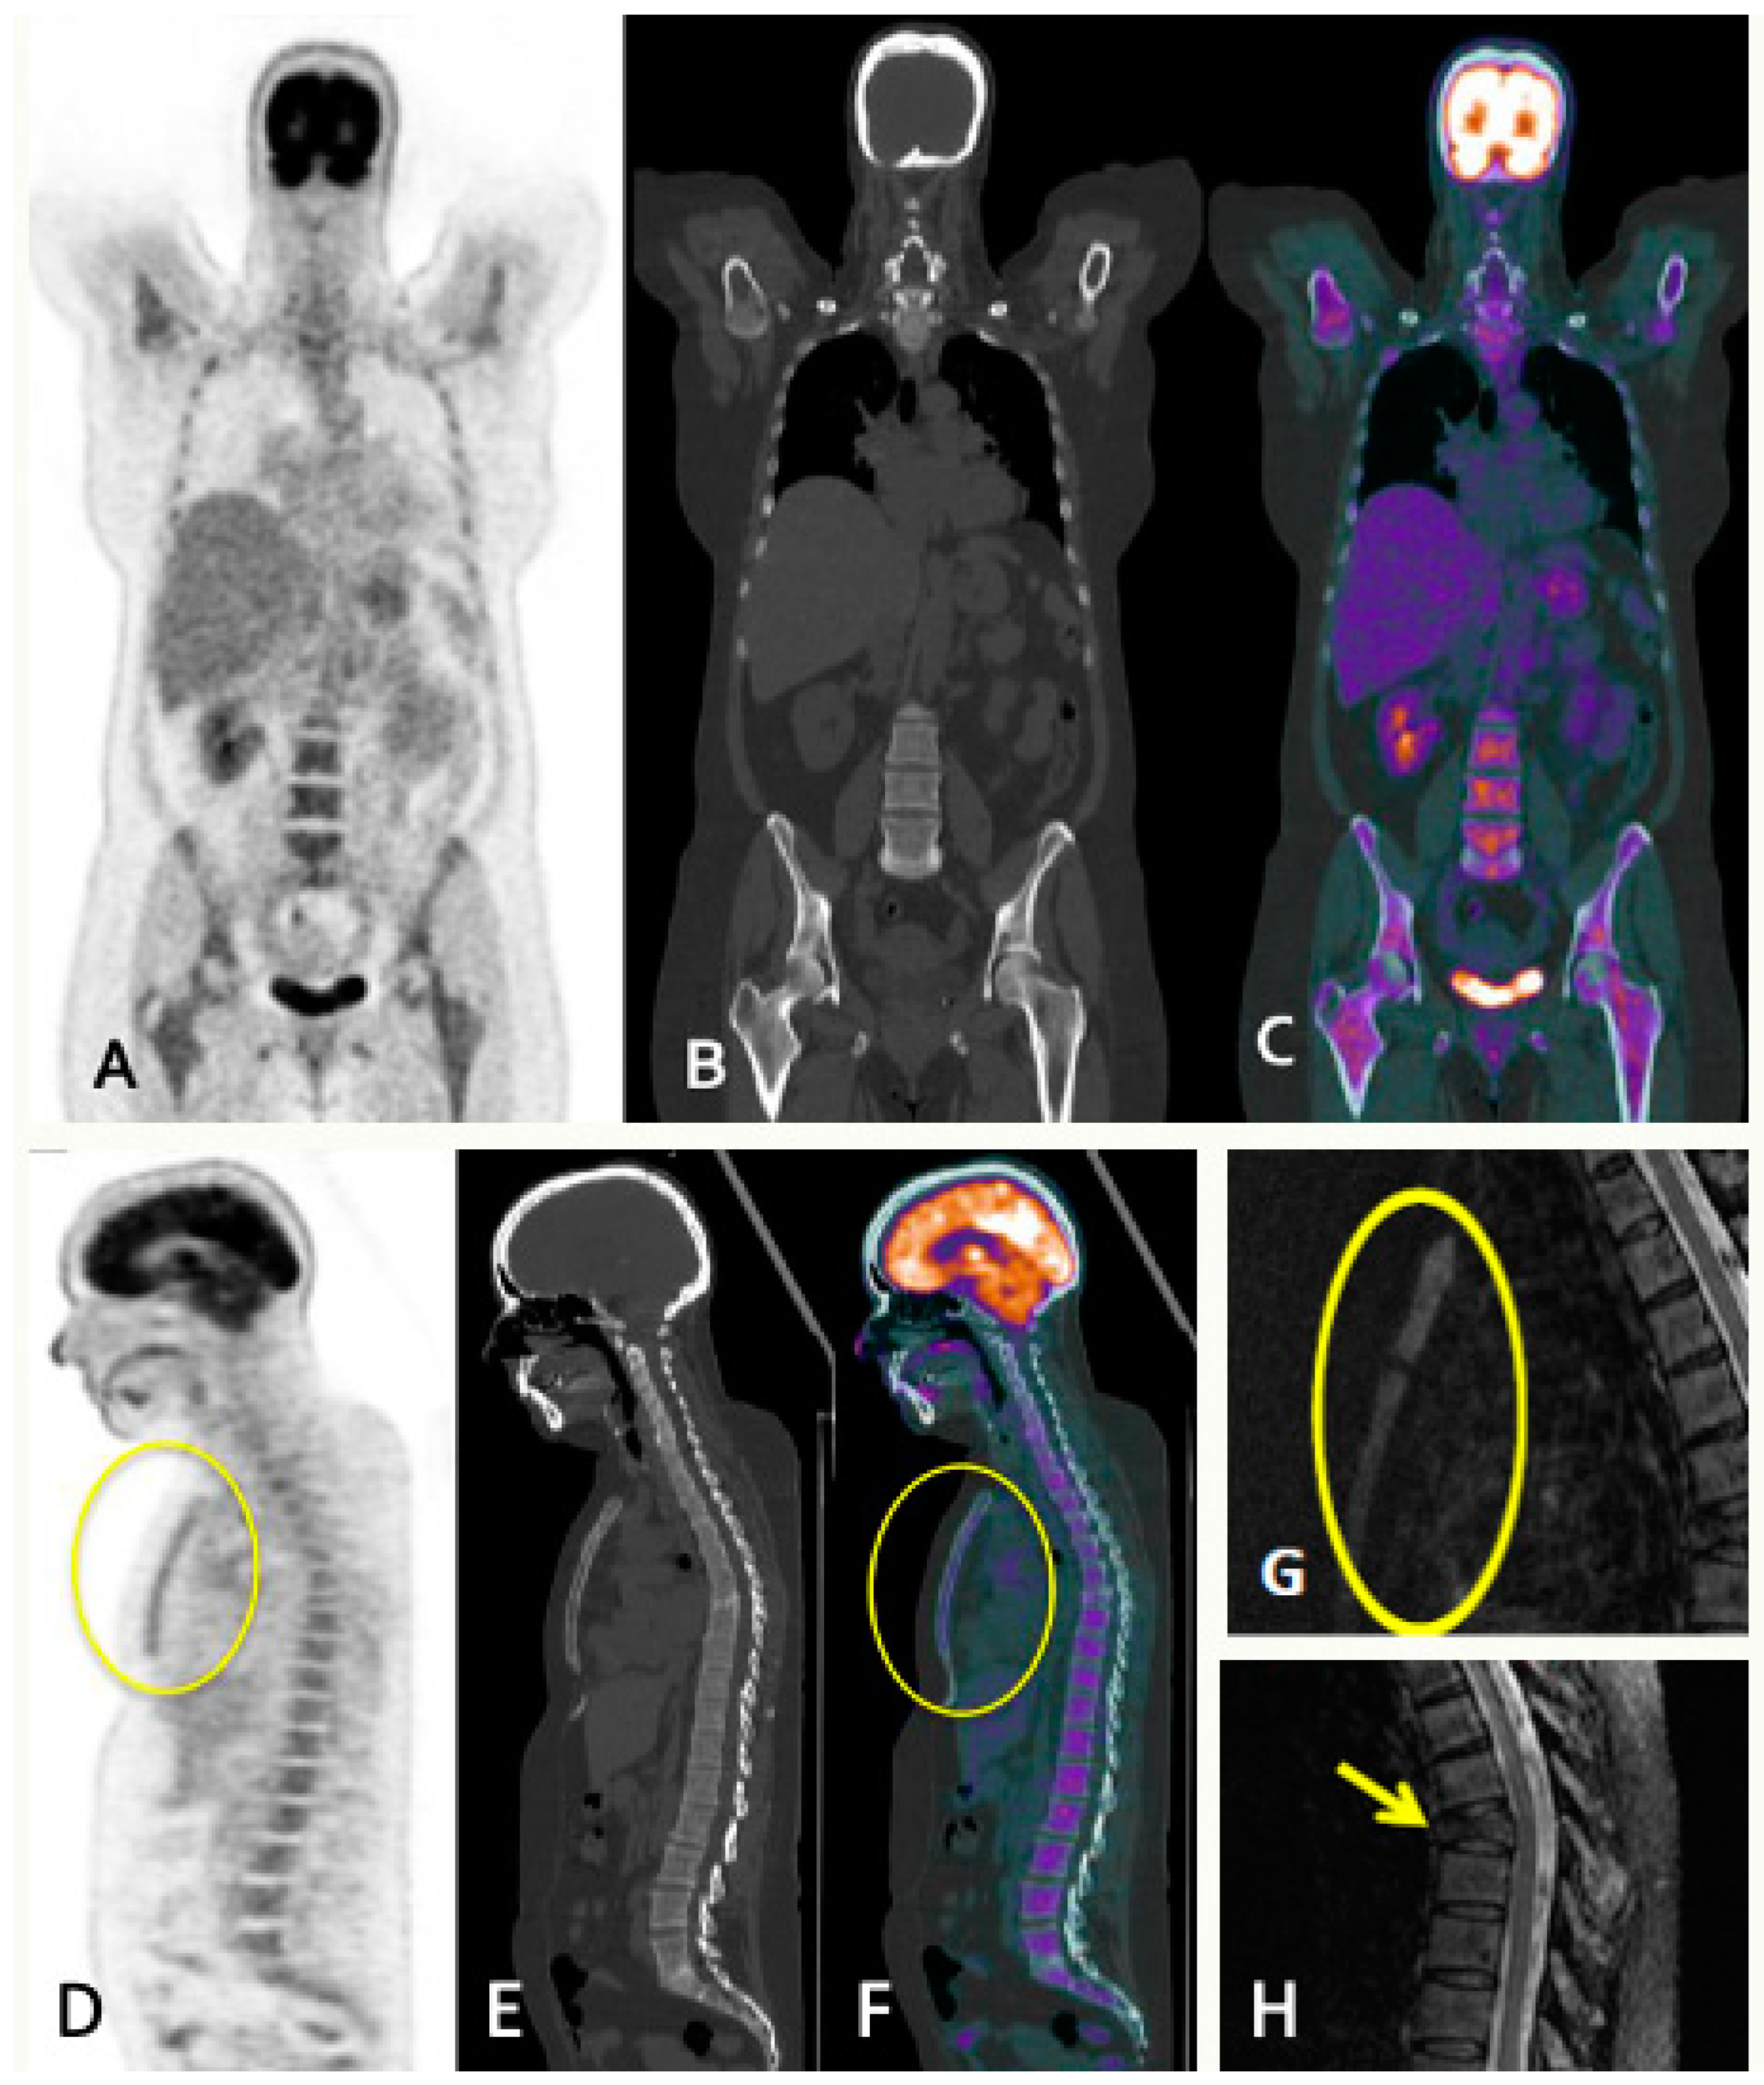

5. PET

5.1. PET/CT

5.1.1. Technique and Image Analysis

5.1.5. FDG-PET/CT vs. WBMRI

5.2. FDG-PET/MRI